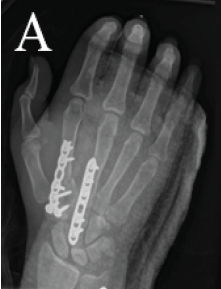

Bridge Plating of Second and Third Carpometacarpal Fracture Dislocations: A Case Report of Rare Injury

Taylor Coates , Kaela Frizzell Hutchinson